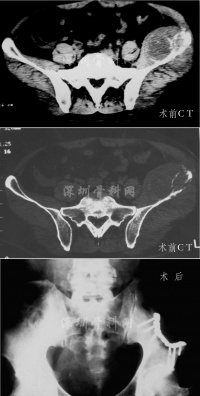

影像学表现[编辑 | 编辑源代码]

少数情况下,当肿瘤贴近骨骼时,可能显示浅表性骨质溶解骨膜反应骨扫描检查对邻近的骨反应很敏感。很少见到病灶的钙化骨化,但有时也可在肿瘤周围或肿瘤内见到。血管造影可显示其与其他恶性肿瘤所共有的变化。但有时甚至在非常大的肿瘤内,可因组织坏死和出血,而呈现为无血管的影像。主要血管可能移位和受压,但很少被浸润。CTMRI显示为实心的,非均质性肿块。有时可见大的含有液体的囊腔。

病灶呈灶样缺损的透亮区,多有完整边缘,好发于干骺端,经常可见有皮质破坏,并穿透到软组织中去。无明显骨膜反应。X线征象类似于其他原发或继发的恶性肿瘤,无特征性,全身骨扫描和CT检查有助于肿瘤鉴别的来源为髓内或骨外。